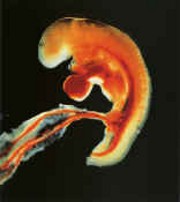

我這個時候的樣子和小豬、小貓、小狗的胎兒沒多大差別。